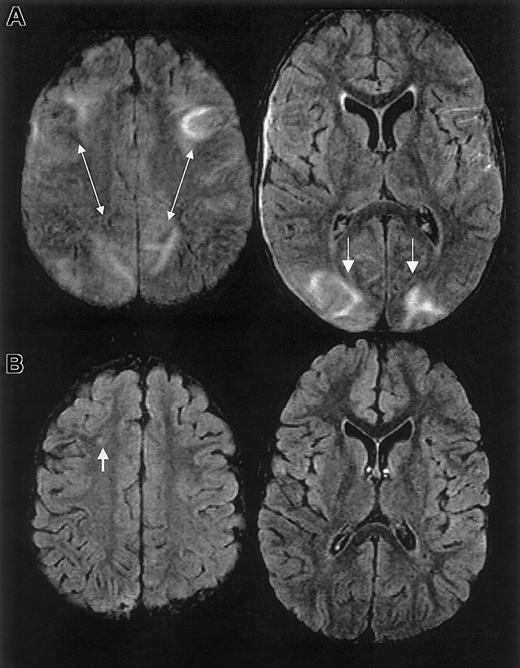

RPLS is difficult to distinguish from acute cerebral infarcts clinically and radiographically. The distinction is important because cerebral infarction implies irreversible damage and warrants blood transfusion therapy for an indefinite period. Conversely, RPLS is potentially reversible but may require judicious hypertensive management. In this case series, 2 patients were originally diagnosed as having cerebral infarcts according to the clinical reading of the MRI, one of whom was subsequently determined to have RPLS and the other with cerebral hemorrhage. Appropriate MRI techniques and interpretation play a key role in differentiating RPLS from cerebral infarct (Figure 4). Both RPLS and cerebral infarct present with T2-weighted hyperintensities. DWIs typically show hyperintense signal in cerebral infarcts, whereas DWIs in RPLS are ambiguous because of T2 shine-through effects.8 14 Producing images of the diffusion coefficient eliminates this ambiguity.

Characterization of T2-weighted hyperintensities on MRI of the brain distinguishing cerebral infarct from reversible posterior leukoencephalopathy syndrome (RPLS).

DWI indicates diffusion weighted image; DC, diffusion coefficient.